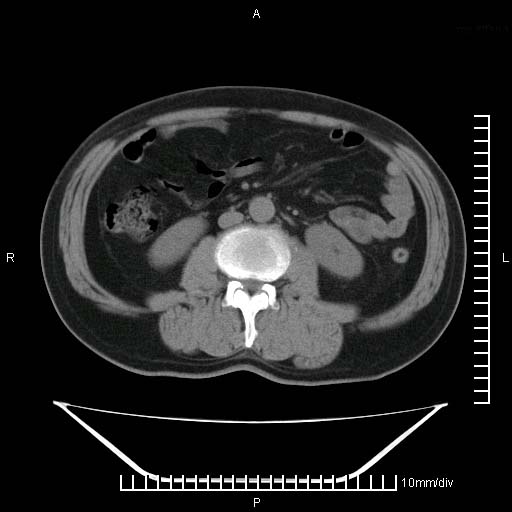

标题: CT25082:肝脏增强:男性,70岁 [打印本页]

标题: CT25082:肝脏增强:男性,70岁

患者以心脏疾病收住院,腹部无明显症状,b超查肝脏有占位。

牛眼征,中心坏死无强化,外缘强化,最外缘又见低密度,考虑转移,与脓肿鉴别

肝内多发转移瘤,右下肺炎症并少量胸水。胃壁增厚建议胃镜,胰尾部“病变”为肠管。

1)肝脏多发性转移瘤(不排除胰尾癌转移所致可能)。2)腹水。3)右侧少量胸腔积液。

ct25082 结果:转移瘤

外院mr结果:胰尾恶性占位。

肝多发低密度灶;轻度强化,较水密度高,考虑转移,不排除肝脓肿